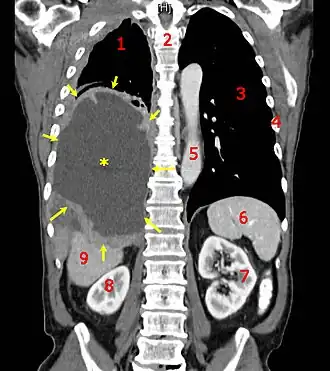

Tomografia computadorizada mostrando um mesotelioma maligno. 1 & 3, pulmões, 2 espinha dorsal, 4 costelas, 5 aorta, 6 baço, 7 & 8 rins e 9 fígado